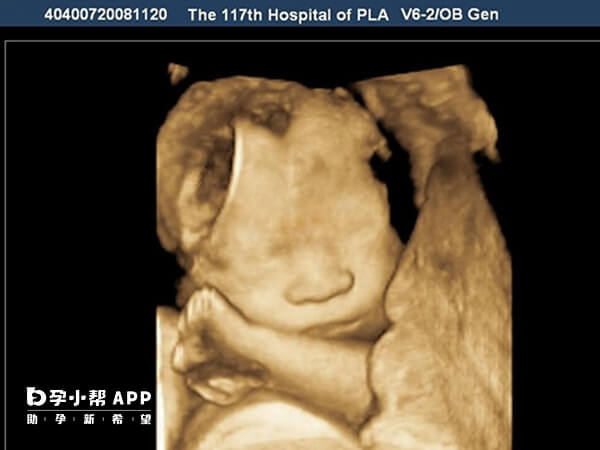

NT检查主要用于孕早期筛查胎儿染色体异常(如唐氏综合征)和结构畸形的风险。通过测量胎儿颈部透明层厚度,若NT值异常(>3mm),提示染色体异常风险增加,需进一步检查(如无创DNA或羊水穿刺)。在试管治疗中,之所以没必要进行nt检查,原因如下: